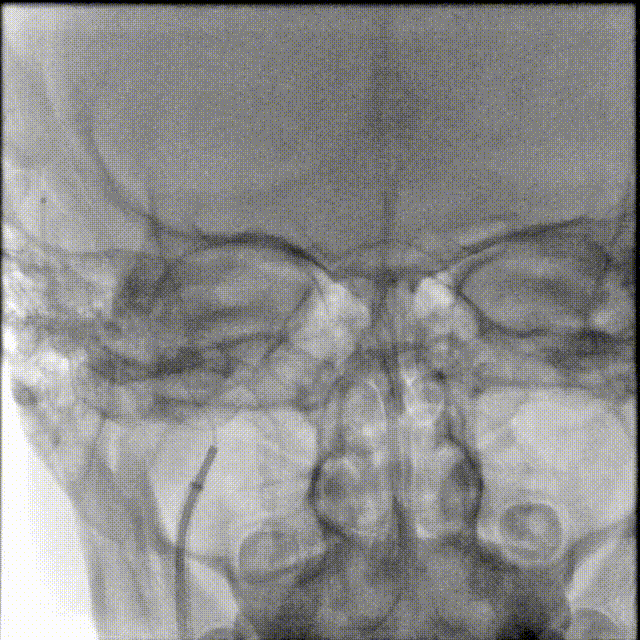

二.术前检查

术前CTA/CTP检查,动脉成像未见明显异常,平扫CT可见右侧横窦区域高密度、左侧顶叶片状高密度,窦汇区域、上矢状窦区域高密度充盈。随后紧急性头颅MRV检查,MRV提示上矢状窦及右侧横窦区域不显影。

1A

1B

1C

1D

1E

图注1:1A/1B 平扫CT可见右侧横窦、窦汇区域高密度,额顶叶片状高密度灶

1C 通路CTA检查动脉像未见特殊

1D/1E MRV冠状位及侧位可见上矢状窦及右侧横窦消失,左侧横窦乙状窦部分显影